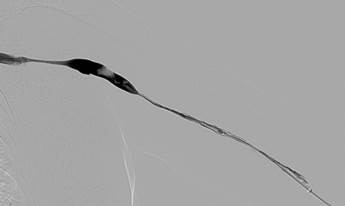

Estenosis subyacente en el arco de la vena cefálica responsable de la trombosis.

Fistulograma tras la primera pasada con un catéter DVX de AngioJet (N. B.: no se usaron trombolíticos).

Fistulograma tras la segunda pasada con un catéter DVX. Se ha identificado otra estenosis hacia la mitad de la FAV.